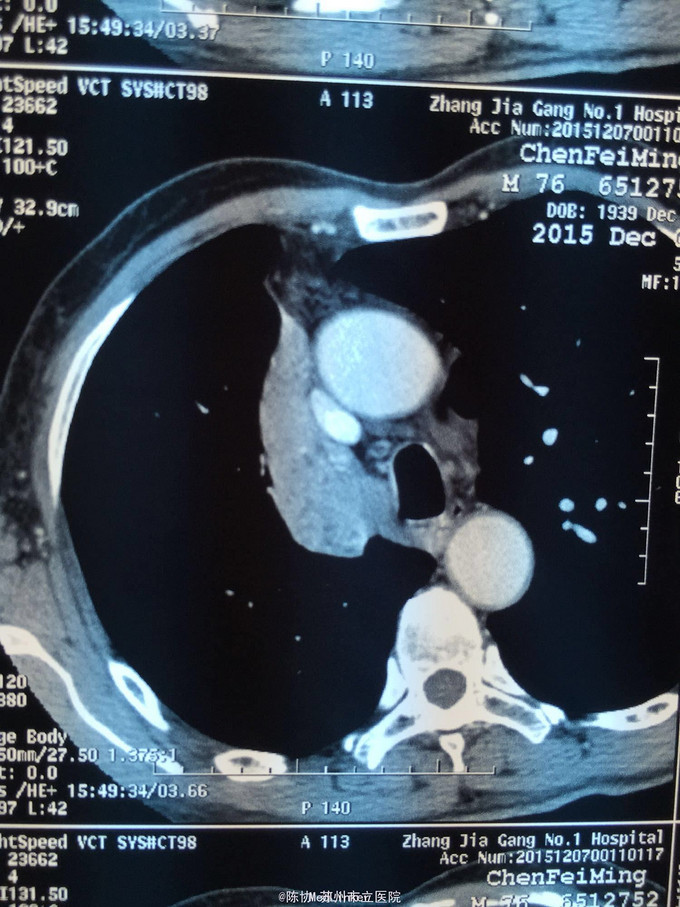

主诉:体检发现右上肺不张半月 77岁男,半月前体检发现右上肺不张,无不适。无消瘦,无咳血,无干咳。去年4月右上肺炎,抗生素治愈,当时CT未见肺肿块。入院支气管镜发现右上支气管开口组织增厚闭塞,开口近侧有隆起约3x3平方毫米,取活检5块病理示中度非典型增生。CT提示在右侧主支气管外侧有30x30平方毫米块影,压迫右上支气管开口处。三大常规和生化检查正常,肿瘤指标正常,TAP正常。

右侧中央型肺癌 重做支气管镜,精于定位找到病症组织,获得病理诊断来指导治疗。 胸外科医生不建议手术,理由是肿瘤位置靠近主支气管和气管,袖状切除不一定看干净。 请问正确的诊断,和比较合理的治疗方法是什么?求助大家思考评论